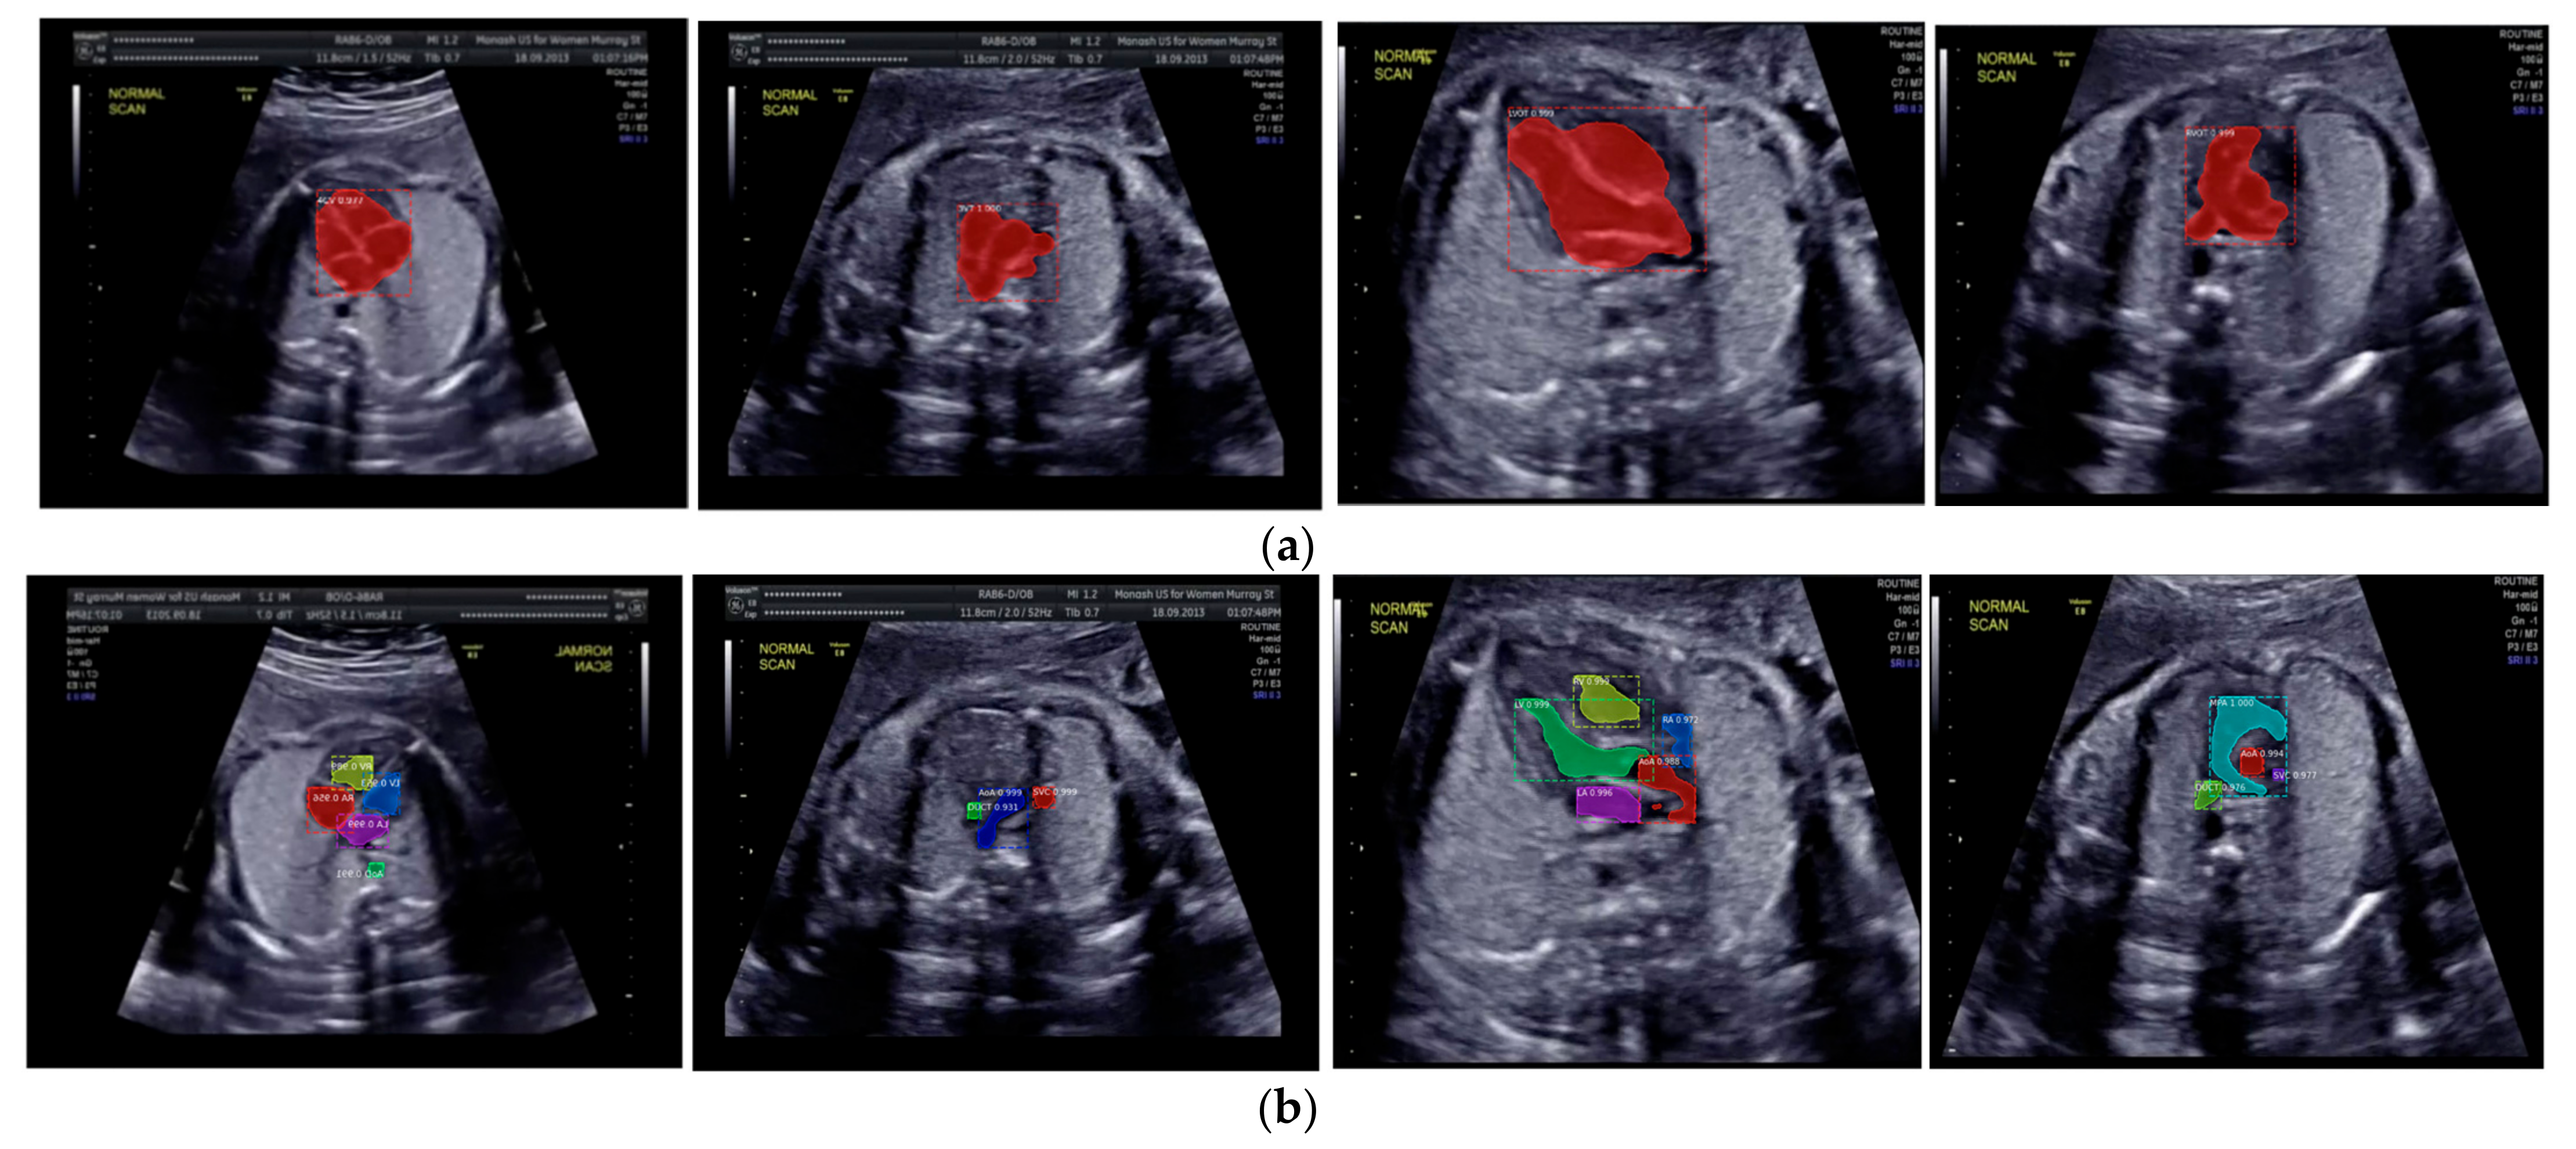

The IoU and DCS performance shows that the instance segmentation with the ResNet50 architecture as the backbone produced excellent predictions for all chambers in each view. Therefore, the Mask-RCNN with the ResNet50 architecture as the backbone of RPNs could segmented and detected the object based on the annotated RoI. In Figure 10a, the sample of segmentation result of fetal standard heart view is provided, and Figure 10b shows the heart chamber segmentation is presented separately. The standard view segmentation, to mark the shape of the cross sectional of the fetal heart, and the heart chambers segmentation, to show the part of each cross-sectional, belong here, whereas in Figure 11a–d, we experimented on two combinations, in such process a fetal heart view and heart chamber is merged, with about 17 heart chamber objects and four heart standard views to predict. Figure 11a,d shows the sample of segmentation results with different colors, but each object has the same description as Figure 10a,b. Based on the proposed model, all objects can be predicted with satisfactory performance (about 96.59% mAP, 79.97% IoU, and 89.70% DCS). The high mAP shows that the object detection process based on the proposed model obtained the overlapping area between the annotated and predicted RoIs of each bounding box close to 100%. The proposed Mask-RCNN model with ResNet50 yielded a 3.41% error in prediction between the annotated and predicted RoIs.

Figure 10.

The sample segmentation result of standard view and heart chamber for normal heart anatomy structure: (a) red color contour denotes the fetal heart boundary segmentation in each view, from left to right are 4CH, 3VT, LVOT, and RVOT; (b) heart chamber segmentation in each view from left to right are 4CH (red: RA, purple: LA, yellow: RV, and blue: LV), 3VT (green: DUCT, blue: AoA, and red: SVC), LVOT (green: LV, red: AoA, blue: RA, and yellow: RV), and RVOT (green: DUCT, cyan: MPA, red: AoA, and purple: SVC).

Figure 11.

Fetal heart view with heart chamber segmentation in (a) 4CH, (b) 3VT, (c) LVOT, and (d) RVOT for normal heart anatomy structure. Fetal heart view boundary and heart chamber part as the same description with Figure 10.